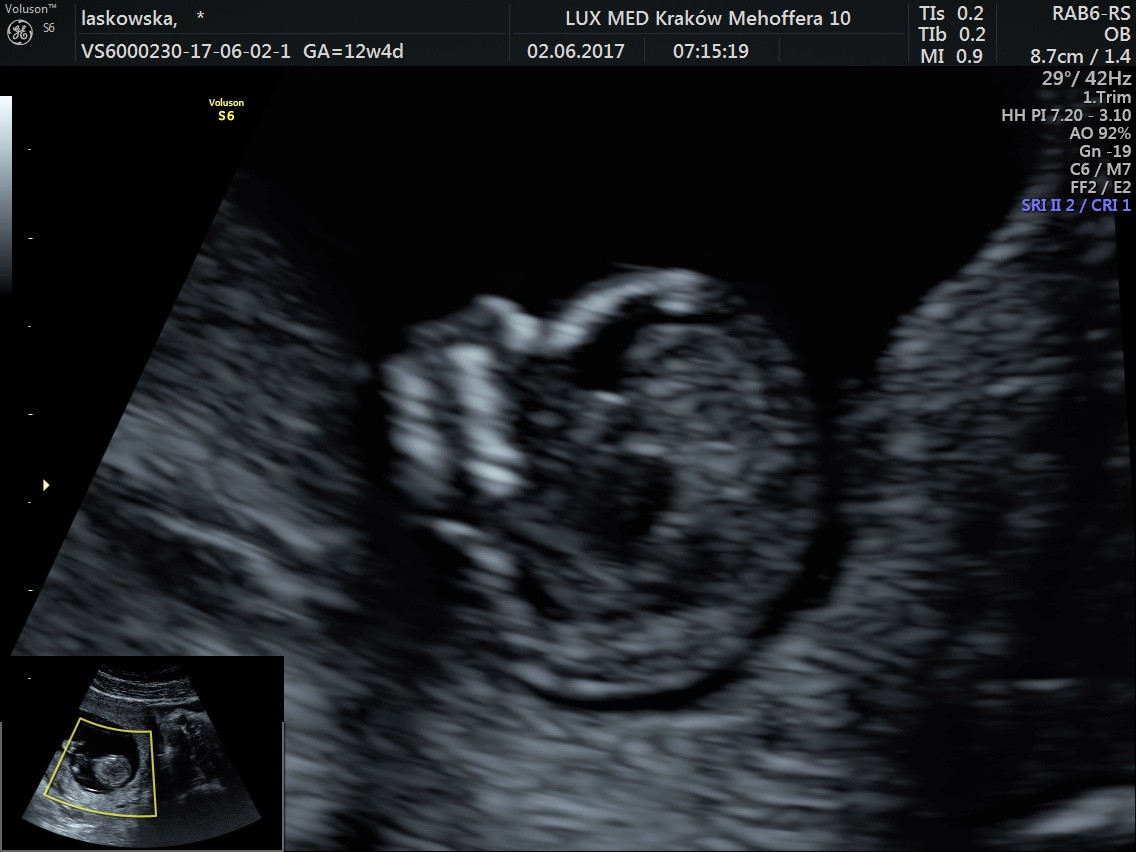

Uparte stworzenie nie chciało współpracować,bo się przecież wyspać musi, ale udało się sprawdzić co najważniejsze. Wielkość 5.92 cm, Przezierność książkowa, kość nosowa - jest, serduszko biło 160/min, móżdżek piękny, oczka najsłodsze na świecie, rączki dwie są, nóżki tak samo, widzieliśmy pęcherz i żołądeczek. Przepływy krwi w porządku. Krótko mówiąc bardzo niskie ryzyko wad genetycznych, Fistaszek jest zdrów jak rybka. Terminy nam się troszkę pozmieniały: OM 11.12.2017, USG 12.12.2017, więc zaraz zrobię poprawki w kalendarzu. Kolejna wizyta 31.07, ale będę patrzeć - może coś się zwolni parę dni wcześniej

Zdjęcia: